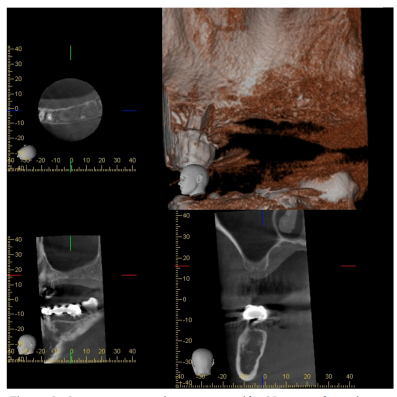

Tres meses más tarde, la paciente acudió de nuevo a la consulta con la finalidad de rehabilitar las ausencias de 25, 26 y 27, solicitándose un estudio mediante CBCT, en el que se observó una altura de1,63 mm y 11,6 mm de anchura (Figura 3).

Transcurridos dos mes y medio, se solicitó un nuevo CBCT donde se observó una altura de 12 mm y anchura de 11,6 mm (Figura 10), por lo que alcanzados los tres meses se procedió a la colocación de los implantes.